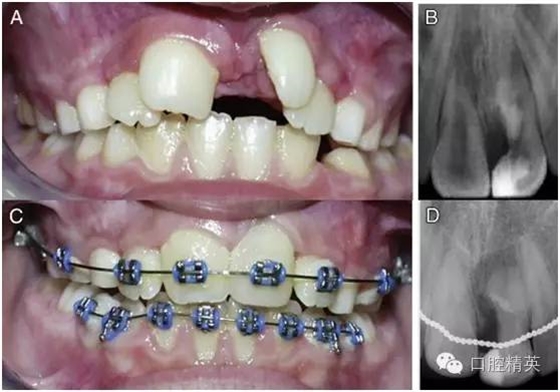

正常隨訪 12 周之后,患牙未出現(xiàn)異常癥狀(圖 3-A),于是按計(jì)劃開始對(duì)患者進(jìn)行牙齒的矯正。從骨頭和牙齒來(lái)看,患者都表現(xiàn)出了遠(yuǎn)中錯(cuò)頜的關(guān)系,按照安氏分類法,患者被診斷為安氏 2 類 1 分類錯(cuò)頜畸形。患者頜骨發(fā)育基本正常,上頜稍后縮,但未出現(xiàn)反頜。上頜切牙區(qū)稍擁擠。

圖 3 正畸前與正畸后期資料。(A)正畸前口內(nèi)像,此時(shí)多生牙部分已被切除,露髓處已經(jīng) MTA 蓋髓,且正常隨訪一段時(shí)間后未見其他異常癥狀出現(xiàn)。(B)正畸前患牙根尖片。(C)正畸治療將要結(jié)束時(shí)的口內(nèi)像,此時(shí)患牙牙冠已經(jīng)參照右上中切牙用復(fù)合樹脂進(jìn)行了美學(xué)修復(fù)。(D)正畸后患牙根尖片。

整個(gè)正畸過程持續(xù)了 3 年半(圖 3-C)。正畸完成治療后,為了獲得最終的美學(xué)效果,患牙剩余部分參照右上中切牙的外形和顏色用樹脂做了充填修復(fù)(圖 3-C)。將術(shù)前根尖片(圖 3-B)與正畸后根尖片(圖 3-D)相比較可以發(fā)現(xiàn),患牙最終表現(xiàn)出了良好的治療效果。